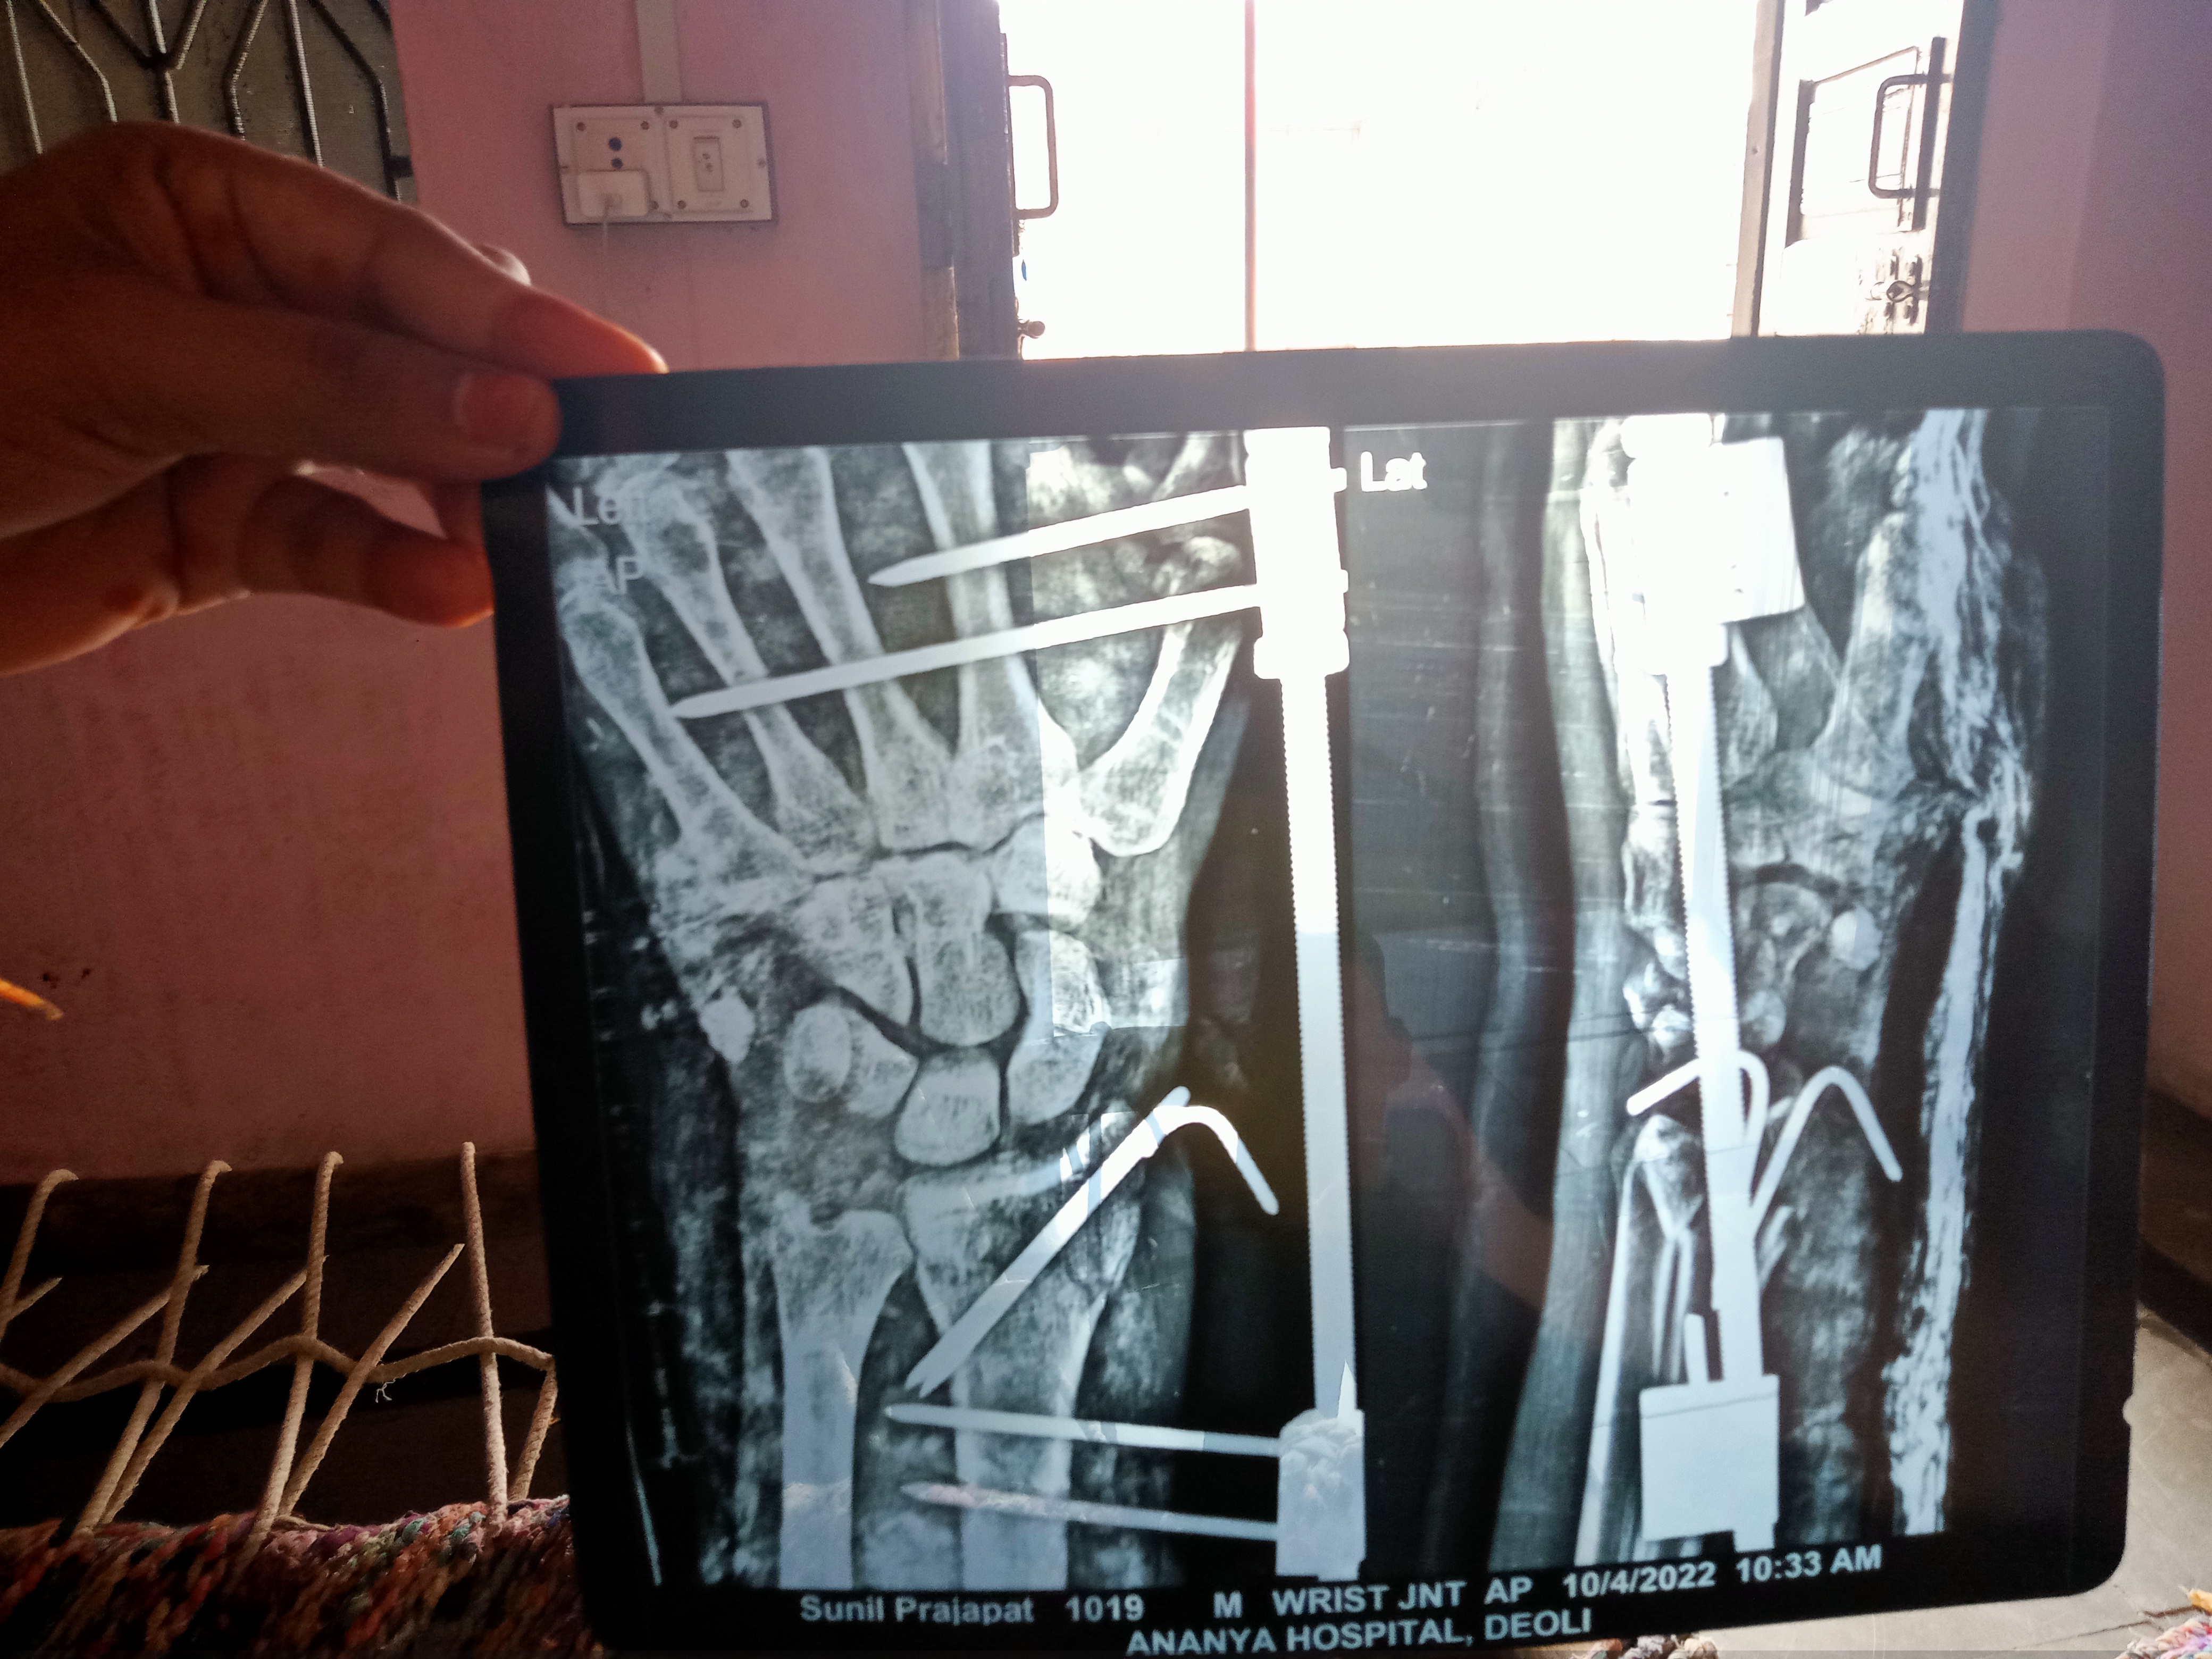

Sir mere 14din ho gye hath ke Joint me Hadi tuti ya, fartucer he aur sir kithne din me theek hoga is exry ko dekhr bto lagbhag kithne me theek hoga

Sir Mera opraction hua tha 13din phle hath ka joint ka Jo sir kithne din think hoga au upar ki trf bolt jasa laga h  usko kithne din bad niklge aur is exry..dekhe ke aap bto ab kithne din lagge,,

Sir isme Hadi tuti ya fartucer

Hadi tuti yr,, Fartucer he